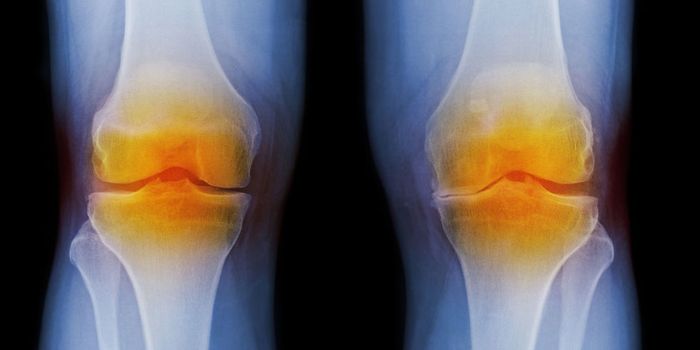

NOV 11, 2021Cell & Molecular BiologyWhile arthritis may not cause pain all the time, when it flares, it tends to recur in the same joints. This can create s ...

JUN 15, 2019Cell & Molecular BiologyIn RA, cells of the immune system mistakenly attack the joints, and cause the painful inflammation that is a hallmark of ...

SEP 26, 2022ImmunologyResearchers have found that a protein called sulfatase-2 may play a significant role in the tissue damage caused by rheu ...

SEP 07, 2021ImmunologyScientists have developed a new cell therapy for arthritis that becomes activated in the presence of inflammation. When ...

MAY 15, 2017ImmunologyA biochemical compound called adenosine is both the cause of osteoarthritis and the subject of promising research for a ...